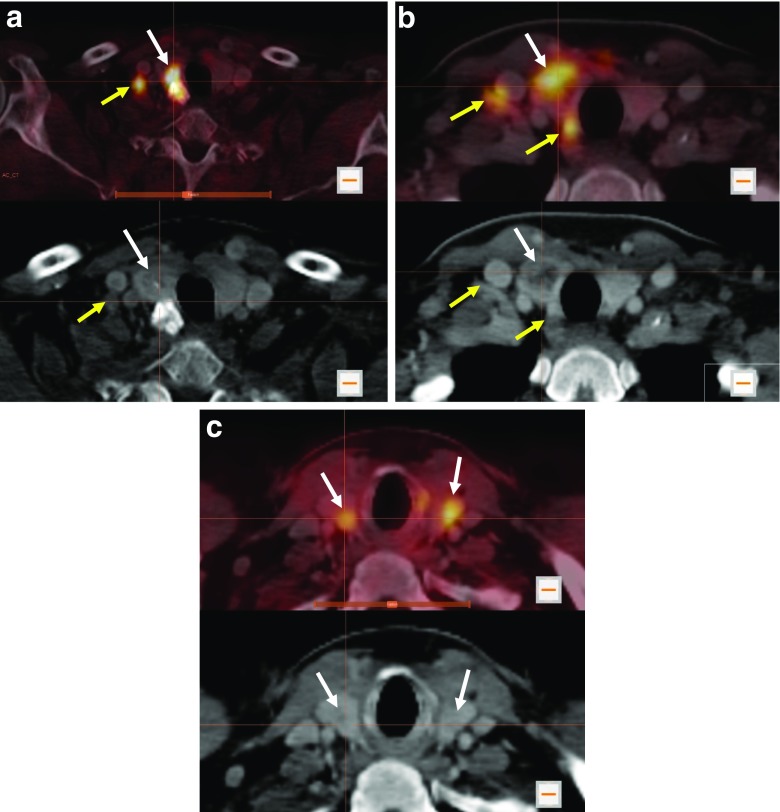

[18F]DOPA PET/CT showed increased DOPA decarboxylase activity in the primary tumour of 28 patients with a maximum SUV (SUVmax.) of 10.5 ± 4.2 (mean ± standard deviation; representative examples are shown in Fig. 1a, b). One patient presented with bilateral suspicious thyroid nodules. Both nodules revealed increased DOPA decarboxylase activity (Fig. 1c). However, there was no evidence of increased DOPA decarboxylase activity in the primary tumour in only four patients. Preoperative LN staging with [18F]DOPA PET/CT showed N0 in 20 patients, N1a in 1 patient, and N1b in 11 patients. In 6 of the patients with stage N1b, [18F]DOPA showed bilateral suspicious LN in neck regions and in one patient showed suspicious LN in the superior mediastinum outside the neck region (Figs. 2a and 3b).

Fig. 1.

Initial [18F]DOPA PET/CT in patients with suspicious thyroid nodules prior to total thyroidectomy and lymph nodes dissection. a Increased DOPA uptake in the primary tumour in the right thyroid lobe (white arrows) and in a right lateral neck lymph node at level IV (yellow arrows) in a 61-year-old male patient. b Increased DOPA uptake in the primary tumour in the right thyroid lobe (white arrows), in a lateral neck lymph node at level IV and in a central (paratracheal) lymph node at level VI (yellow arrows) in a 47-year-old female patient. c Increased DOPA uptake in the primary tumour in both thyroid lobes (white arrows) in a 48-year-old male patient